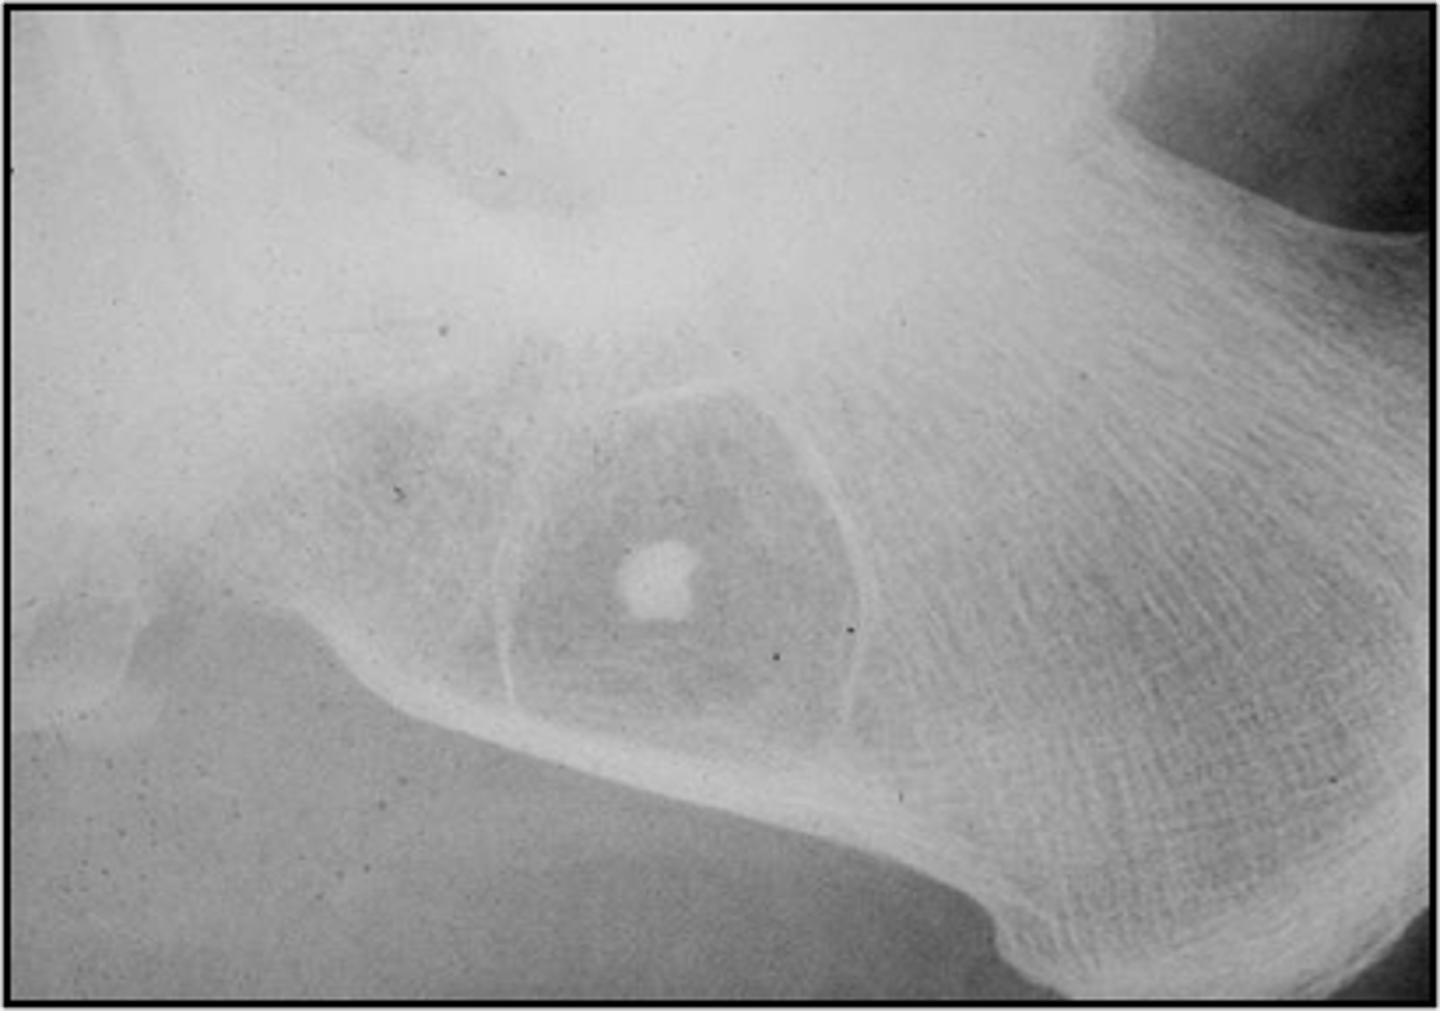

- Asymptomatic

- Central target sequestrum

- Calcaneus

Target sequestrum

ID sign of intraosseous lipoma